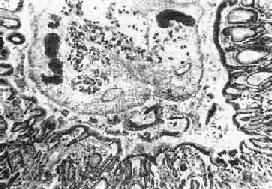

图19-13 肝华支睾吸虫病 胆管内可见虫体,胆管粘膜有腺瘤样增生及炎症 成虫在肝内胆管寄生,使胆管内胆汁淤积,容易发生继发感染。死亡的虫体、虫卵和脱落的胆管上皮还可以成为胆石的核心,促进胆石形成。 关于华支睾吸虫感染与肝癌(胆管上皮癌)的关系,我国病理学者侯宝璋、秦光煜等曾分别对人体或自然感染的动物(家猫及家犬)进行了观察研究,证实在华支睾吸虫感染的致的胆管上皮腺瘤样增生的基础上,可以发生癌变,在人工感染的家猫实验中也得到证实。至于致癌因素是成虫在胆管内蠕动的机械性刺激或虫体代谢产物和胆汁成分的化学刺激,尚有待进一步研究。 2.胆囊 成虫也可在胆囊内寄生(约占9%),镜下可见胆囊壁有嗜酸性粒细胞及淋巴细胞浸润,而上皮细胞增生多不明显。 3.胰腺 成虫也可在胰腺导管内寄生(占6%~37.5%)引起病变,可能是成虫随胆汁进入胰管,也可能是童虫进入胰管内发育为成虫所致。肉眼观,胰管扩张、增厚。镜下,可见胰管上皮增生,并伴有不同程度的鳞状化生(可达95%)。鳞状化生的程度往往与感染的虫数有关。胰腺实质一般无明显改变,但有报告谓可诱发急性胰腺炎。